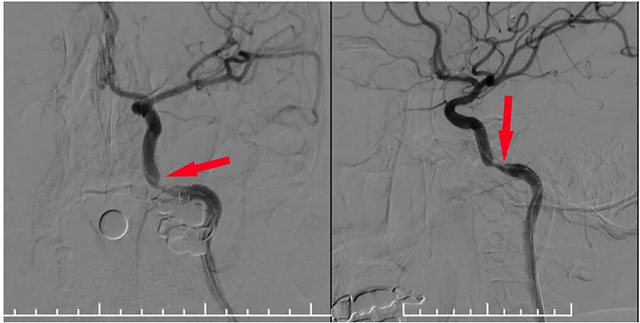

▲ 球囊扩张支架在微导丝导引下到位于狭窄段

术中,张琪博士在刘春医生、周林华医生及医护团队协助下从左侧股动脉穿刺,置入6F导管鞘。将6F导引导管在泥鳅导丝导引下置入左侧颈内动脉,造影明确岩骨段狭窄呈,测量狭窄段长度及近远端血管支架,选择合适支架,随后在微导丝辅助下越过狭窄段超选至C6段,选用4.0*18球扩支架,沿微导丝到位狭窄段,球囊扩张至6atm,即刻释放支架,即刻造影见狭窄明显改善,支架贴壁良好,血流通畅,狭窄段完全覆盖。

▲ 球囊扩张后支架释放狭窄已明显改善